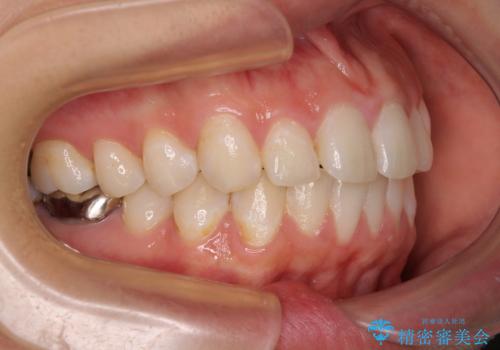

- 銀歯が外れてしまったとのことで来院された患者様です。

上顎奥の粘膜に近い部分で、外れた銀歯の下には大きく虫歯が広がっていました。